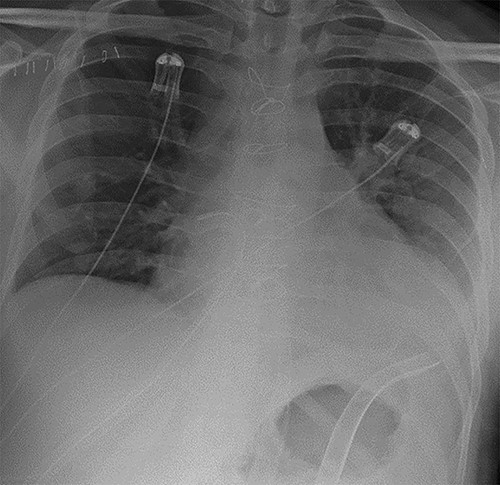

As part of his work-up for cardiac transplantation he was found to be a carrier of the HbS sickle cell trait, with an estimated HbS concentration of 34.4%. Due to his deteriorating condition and the uncertainty as to his candidacy for transplantation [5], the management plan was for mechanical circulatory support as a bridge-to-decision. An axillary IABP was inserted as previously described [6]. Unfortunately, he continued to deteriorate, requiring the implantation of a short-term BiVAD, as previously described [7]. His overall condition improved with BiVAD support—there was recovery of renal and liver function and resolution of pulmonary oedema, as shown in Fig. 2. However, there was no evidence of myocardial recovery, and he was therefore placed on the super-urgent heart transplant waiting list.

Chest radiograph demonstrating biventricular assist device pipes in situ and resolution of previous pulmonary oedema.